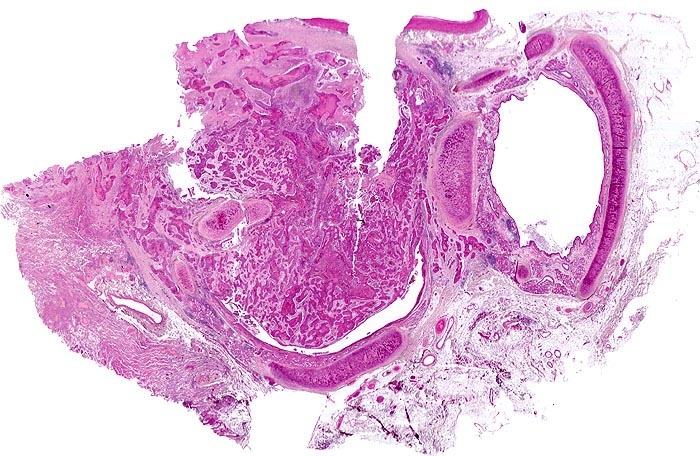

Morphologische Merkmale:

• Zwei Bronchuslichtungen. Eine davon verschlossen durch einen Tumorzapfen.

• Infiltration und Destruktion der Bronchialwand.

• Solide Zellstränge eingebettet in lockeres desmoplastisches Stroma.

• Im Zentrum der Zellstränge grosse Mengen von teils nekrotisch zerfallenden Hornlamellen und Fremdkörperriesenzellen.

• Zytoplasmareiche Tumorzellen mit stachelartigen Interzellularbrücken.

• Vergrösserte hyperchromatische Kerne.

• Mitosen.